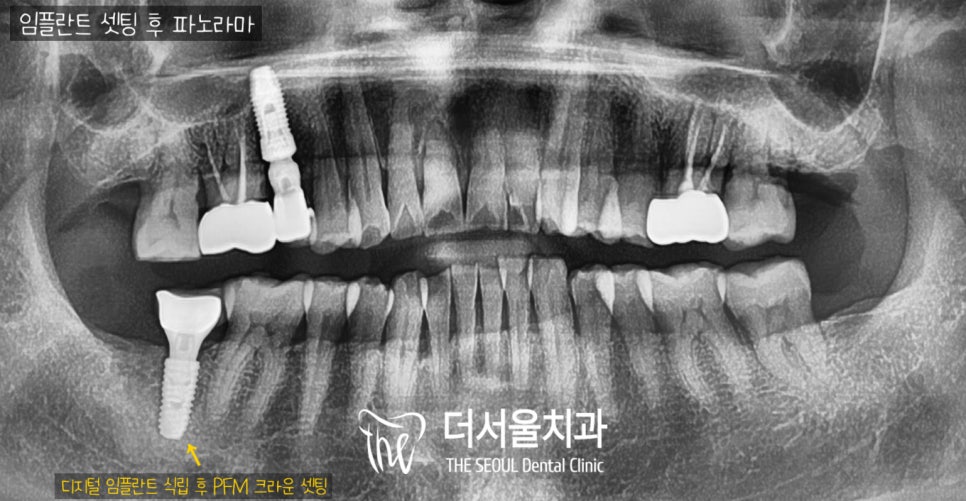

3. 결과

수술은 시작하자 마자

5분만에 끝났습니다. ^^

위에서 말씀드렸다시피

이미 계산된 위치에

절개 없이 바로 심기 때문에

충분히 가능합니다.

끝나고 나서 피도 거의 없고

통증도 없이 신속하게 끝나서

환자께서 결과에 만족스러워 하셨습니다. ^^

치료 기간 : 2022.05.10 ~ 2022.10.26